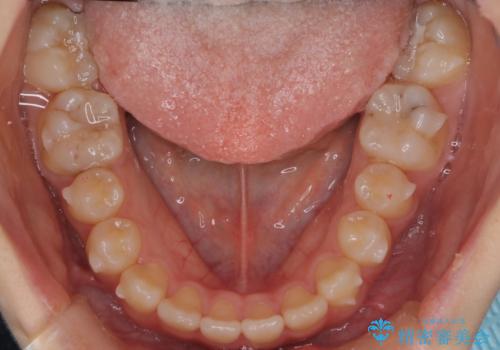

マウスピース矯正で前歯のガタツキを改善! 短期間で治療完了

- 前歯のガタツキが気になるとのことで来院されました。

前歯のガタツキに加え、奥歯の噛み合わせにも問題があったため、マウスピース矯正で治療し改善しました。